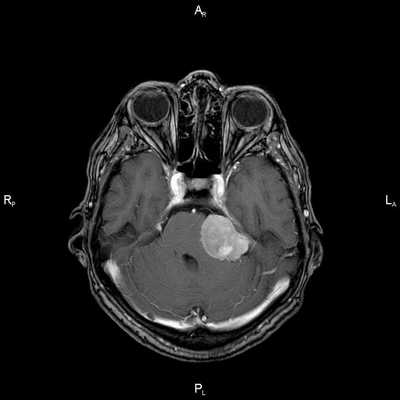

Проблема: жалобы на частые головные боли, снижение слуха (левое ухо), а также шум в ушах (больше слева). Пациент был направлен на МРТ головного мозга в ЦМРТ с целью уточнения диагноза.

Диагноз: Онкология. Менингиома мосто-мозжечкового угла

При МРТ головного мозга в левом мосто-мозжечковом углу определялось больших размеров округлой формы внемозговое патологическое образование, с четкими ровными контурами, широким основанием, прилежащее к твердой мозговой оболочке. После внутривенного контрастирования отмечалось равномерное, выраженное усиление интенсивности МР-сигнала от вышеописанного образования, а также твердой мозговой оболочки. Пациенту был поставлен диагноз (менингиома левого мосто-мозжечкового угла).